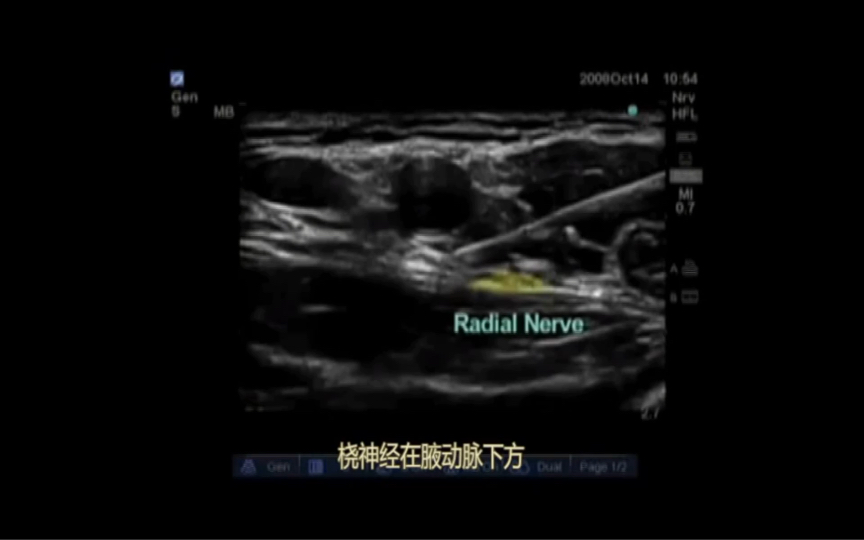

腋路神经阻滞